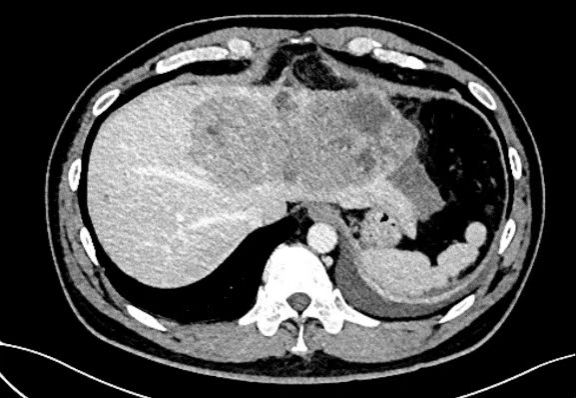

一名四十岁男性患者突发腹痛1天由外院转来。患者有慢性乙肝病史,已经多年未做检查,急诊CT显示:一个直径约16cm×10cm的巨大肝癌充满患者左半肝,挤压侵犯第二肝门肝中静脉(图1,图2)。更危急的是,肿瘤周围大量积液,怀疑肝癌已发生破裂,患者血压90/60mmHg,生命体征岌岌可危。蒋安主任医师接诊后联系输血科董艳迎主任快速输血,迅速纠正休克,使生命体征稳定。